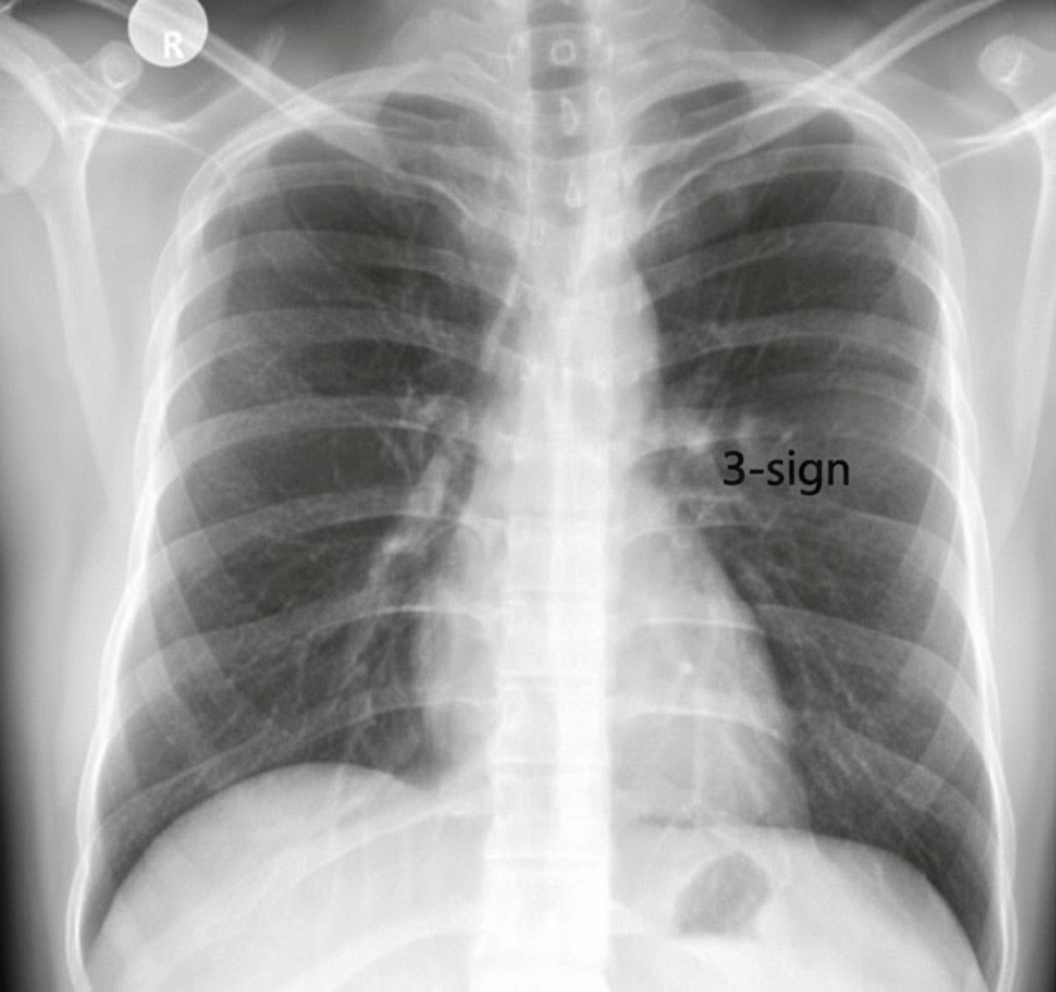

A chest radiograph is obtained from a male patient with hypertension. What is the probable diagnosis?

Explanation: ***Coarctation of the Aorta*** - Classic chest X-ray findings include **rib notching** (ribs 3-8 bilaterally) due to intercostal artery dilatation and the **"3-sign"** at the aortic knuckle from pre- and post-stenotic dilatation. - **Hypertension in a young male** with these characteristic radiographic features strongly suggests coarctation of the aorta as the underlying cause. *Mitral Stenosis* - Chest X-ray typically shows **left atrial enlargement** with a prominent left heart border and **pulmonary edema** patterns. - Associated with **rheumatic heart disease** and presents with dyspnea rather than systemic hypertension as the primary feature. *Transposition of Great Arteries* - Chest X-ray shows a **"egg-on-string" appearance** with a narrow mediastinum and increased pulmonary vascular markings. - Presents in **neonates with cyanosis** and severe heart failure, not hypertension in older patients. *Aortic Stenosis* - Chest X-ray may show **left ventricular hypertrophy** and **post-stenotic aortic dilatation** but lacks rib notching. - Typically presents with **syncope, angina, and dyspnea** rather than isolated hypertension on imaging.